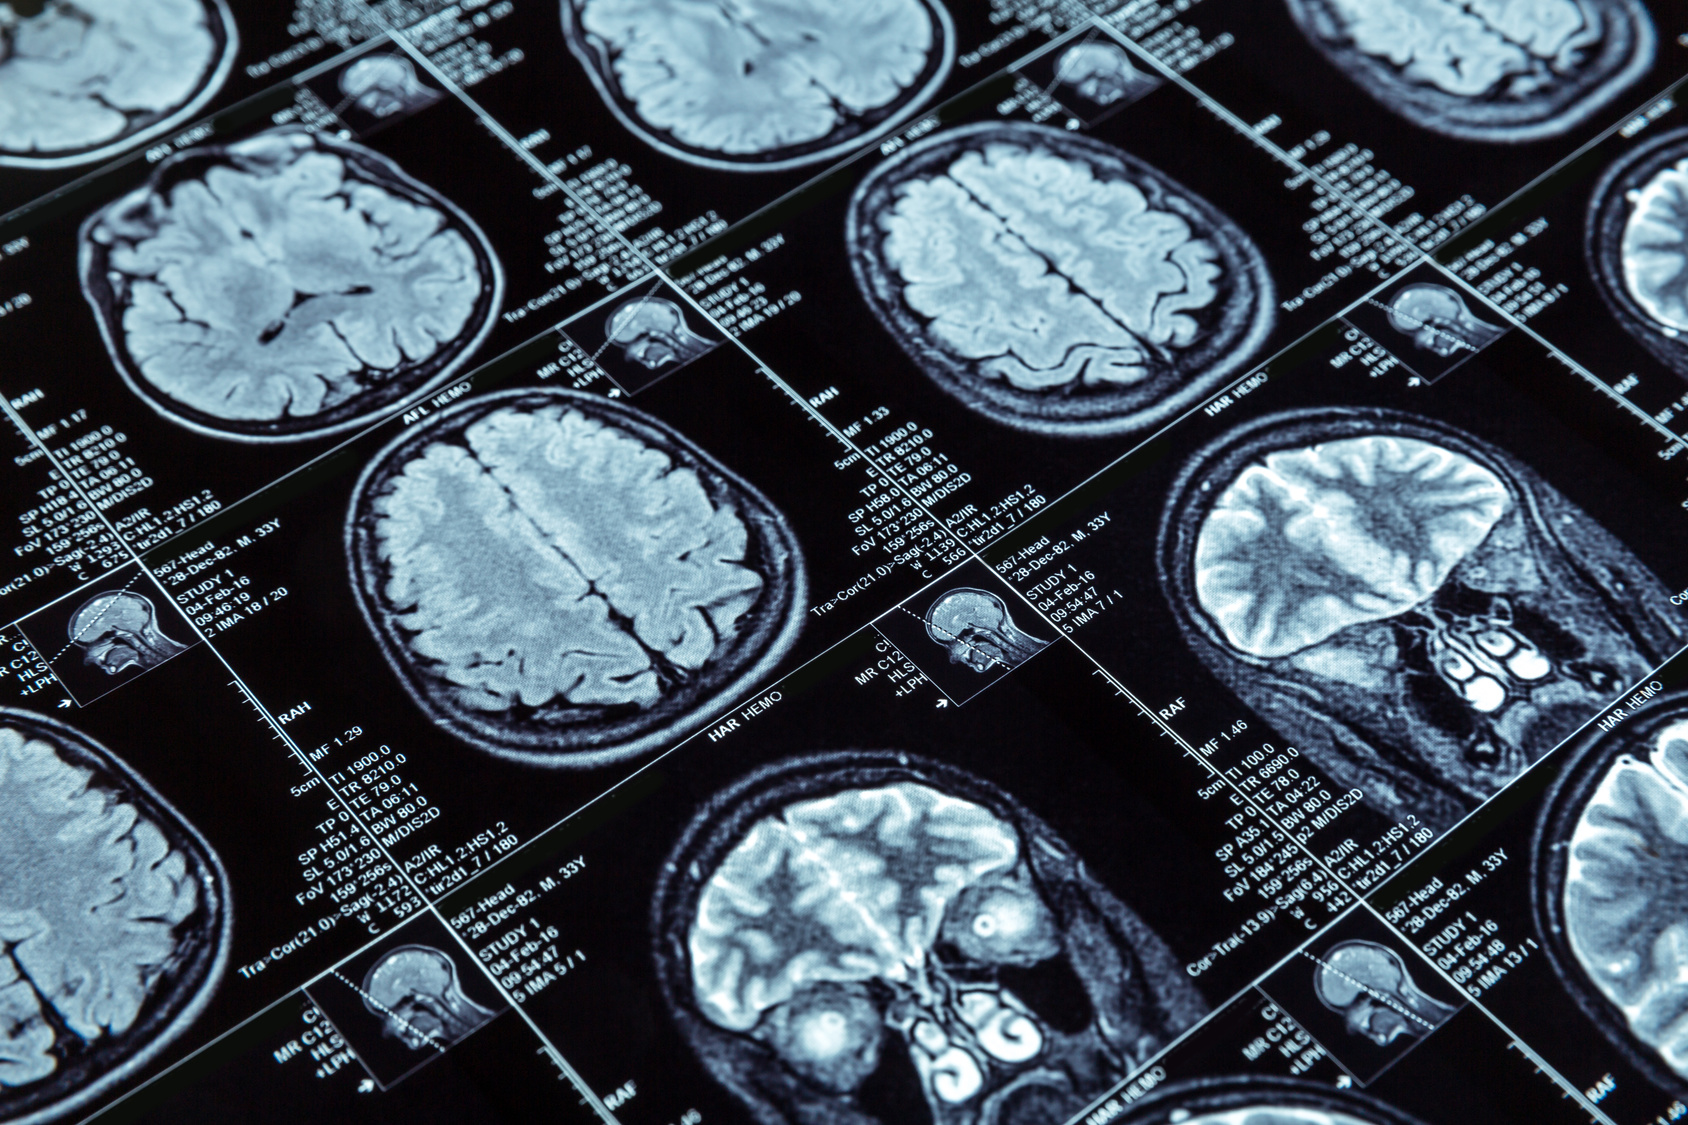

Diagnostik bei Parkinson-Syndromen